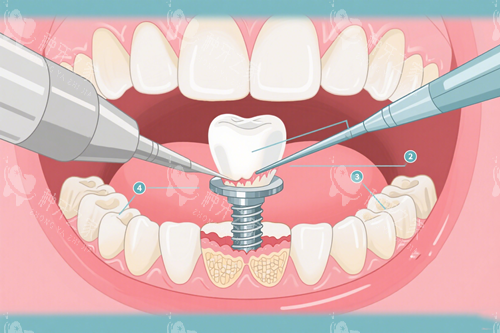

当你决定通过种植牙来修复缺失的牙齿时,很可能已经听说过"骨膜"这个关键角色。但你是否曾疑惑,这个被放入牙槽骨中的小小材料,究竟需要多...